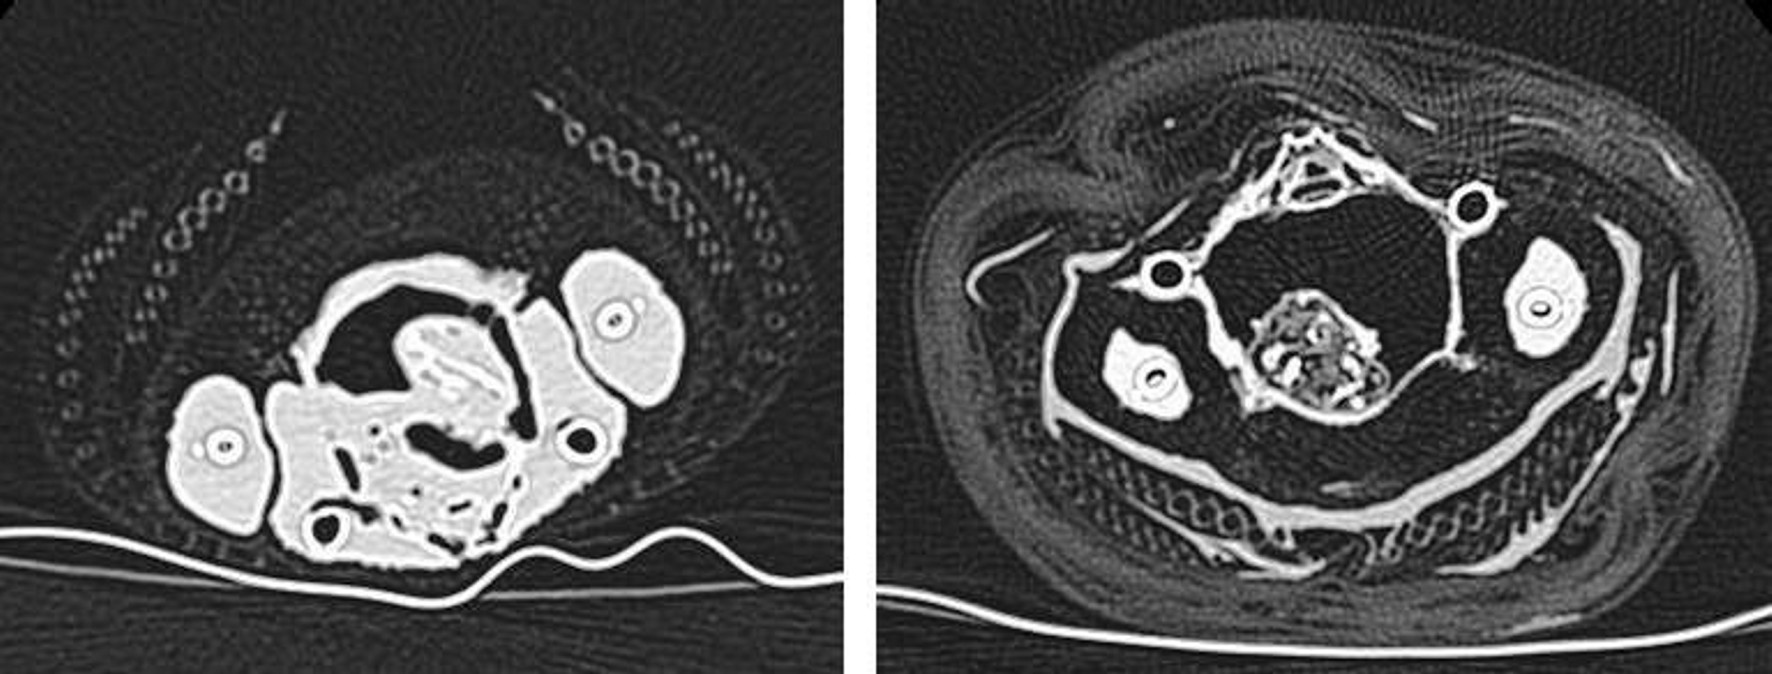

An immature, female Accipiter nisus (See Figure 6) was donated by the Natural History Museum Bird Group, Tring with the purpose of testing the above aims. The specimen named experimental mummy one (EM1) was presented to the Natural History Museum by a member of the public in February 2012 and was dry frozen upon receipt. It was transferred to a dry freezer and kept at -21 °C at the KNH Centre for Biomedical Egyptology, University of Manchester from October-November 2012. Over 72 hours, EM1 was thawed to room temperature and then radiographed (XR and CT) at the Manchester Royal Infirmary2 to ascertain any skeletal damage obtained peri-mortem (See Figure 7). Despite the cause of death being attributed to collision, no trauma was visible and no pathology was evident (See Figure 7). EM1 was then placed in a humidity controlled unit for 48 hours with an average temperature range of 45-48 °C in order to accelerate natural desiccation whilst simultaneously inhibiting bacterial growth (See Figure 8).

The mummy bundle was stored in a fume cupboard and the environmental conditions, both temperature and humidity, in addition to alterations in the appearance, odour and bundle mass, were recorded. Further radiography (XR and CT) was undertaken on three separate occasions post-mummification (at day 5, day 61 and day 229) to document the taphonomic changes.

- The reduction in size of the visceral and muscle tissues; this was clearly noticeable using CT images from pre- and post-mummification (see Figure 13). It appears that desiccation is continuous, even after the anointment and wrapping methods were completed.